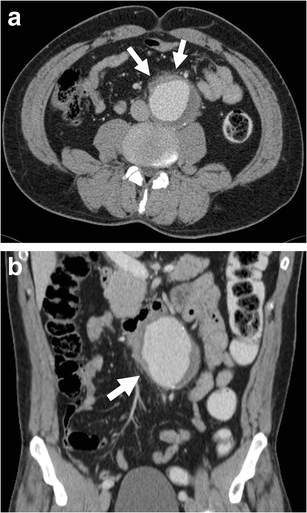

Contrast extravasation

Contrast extravasation. a-b Axial enhanced CT of a 75-year-old woman demonstrates active contrast extravasation (white arrows) from the aneurysm lumen (L) into the retroperitoneal space with massive retroperitoneal haematoma (R)